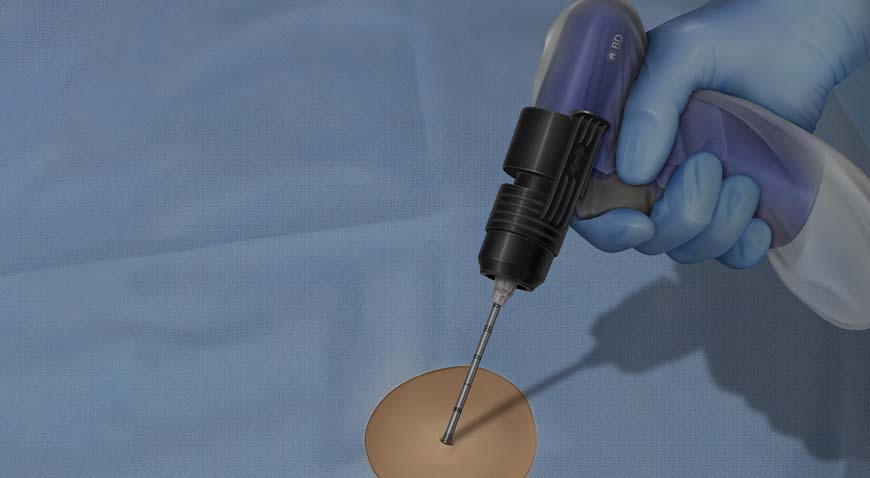

The BD Trek™ Bone Marrow Biopsy System (BD Trek™ Power Driver, BD Trek™ Bone Marrow Biopsy Kit) is intended for bone marrow aspiration and biopsy in adult and pediatric patients age 2 and older.

The BD Trek™ Bone Lesion Biopsy System (BD Trek™ Power Driver, BD Trek™ Bone Lesion Biopsy Kit) is intended for bone biopsy of the vertebral body and bone lesions.

The BD Trek™ Bone Lesion Biopsy System (BD Trek™ Power Driver, BD Trek™ Bone Lesion Biopsy Kit) is intended for bone marrow aspiration and biopsy.